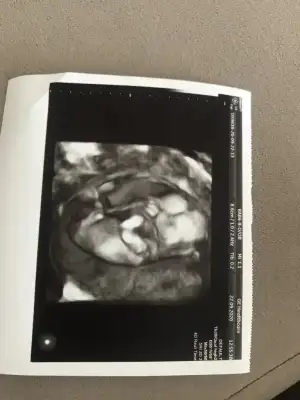

Sonuç belli olsa da bende atayım da hatıra kalsın ikracım hep buraya atmayı hayal etmiştim senın değil harfli tek heceli yazmanı ama kısmet değilmiş hayırlısı olsun

Ikra meyra

içimde kalmasın diye attım

Ikra meyra

içimde kalmasın diye attım

Ordaki hiç pipi kadar büyük gelmedi hayırlısı diyorum tatlımSonuç belli olsa da bende atayım da hatıra kalsın ikracım hep buraya atmayı hayal etmiştim senın değil harfli tek heceli yazmanı ama kısmet değilmiş hayırlısı olsunIkra meyra içimde kalmasın diye attım